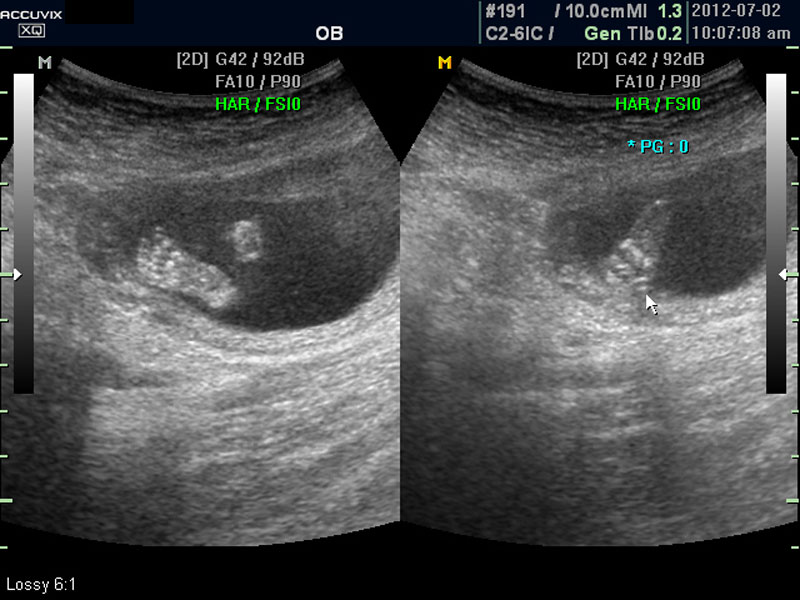

대신 첫번째 사진에서 보는 것처럼 태아의 전체 모습 특히 태아의 등쪽이나 복벽의 이상은 없는지 신경관 결손 등으로 인한 종괴가 있지는 않은지 관찰하며 태아의 복벽이나 등쪽은 일직선으로 매끈하게 보이는 것이 정상입니다.

첫번째 사진에서는 하지 부분은 대퇴부만 일부 보이며 이는 태아가 다리를 구부리고 있고 팔도 이리저리 움직여 머리 위나 목 쪽으로 두는 경우가 많아서 한번에 전체 모습을 찍기가 어려운 경우가 많습니다.

따라서 부분 부분 살펴 보면서 해당 모습을 찍어서 저장하거나 인쇄하여 드리기도 하는 것이며 아래 사진은 태아의 다리 부분을 찍은 것입니다.